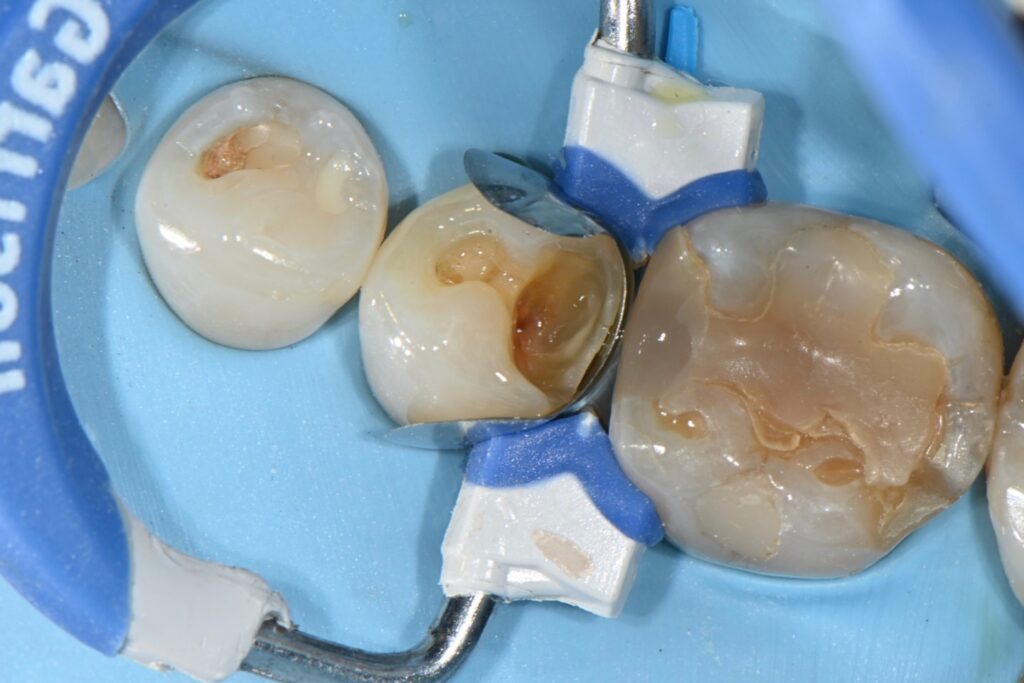

기존 인레이 하방에 이차우식 제거후

신경치료하지 않고 빌드업 완료 케이스입니다

기존의 골드인레이에 문제가 생겨서 오신분입니다

인레이 하방으로 이차우식이 생긴 경우인데요

대부분 인레이가 오래되거나 음식물이 들어가기 시작하면 생기는 현상입니다

골드인레이를 오년정도 사용하셨고

음식물이 너무 많이 끼여서 뒤쪽에 보면

저렇게 이상한 모양으로 레진필링도 타치과에서 받으셨습니다

그냥 음식물이 끼이니까 급하게 하신것 같은데

오히려 저런부분이 골드인레이 하방에

충치가 생기도록 한 것 같습니다

타치과에서 신경치료 크라운 설명을 들었지만

혹시나 하는 마음으로 내원하신 케이스 입니다.

일단 빌드업으로

최소한의 삭제로 신경치료를 하지 않고

치아를 실려 보도록 하려고 하였습니다

충치를 제거해 나가면서

뒤쪽의 이상한 부분도 깔끔하게 정리하였습니다

그리고 그 부분에 빌드업을 해보도록 합니다,

충치를 제거하고 뒤쪽을 다듬은 모습입니다

정리가 그래도 깔끔하게 된듯한데

불안한 부분은 신경이 가까워서 혹시나

신경치료를 들어갈까 걱정했지만

그래도 적절히 빌드업이 가능했습니다

치료가 왼료되는 과정입니다

기존의 인레이보다 음식물이 훨씬 덜 끼면서

깨지지 않고 이차우식에 강한 그런 치료가 왼료되는 과정입니다